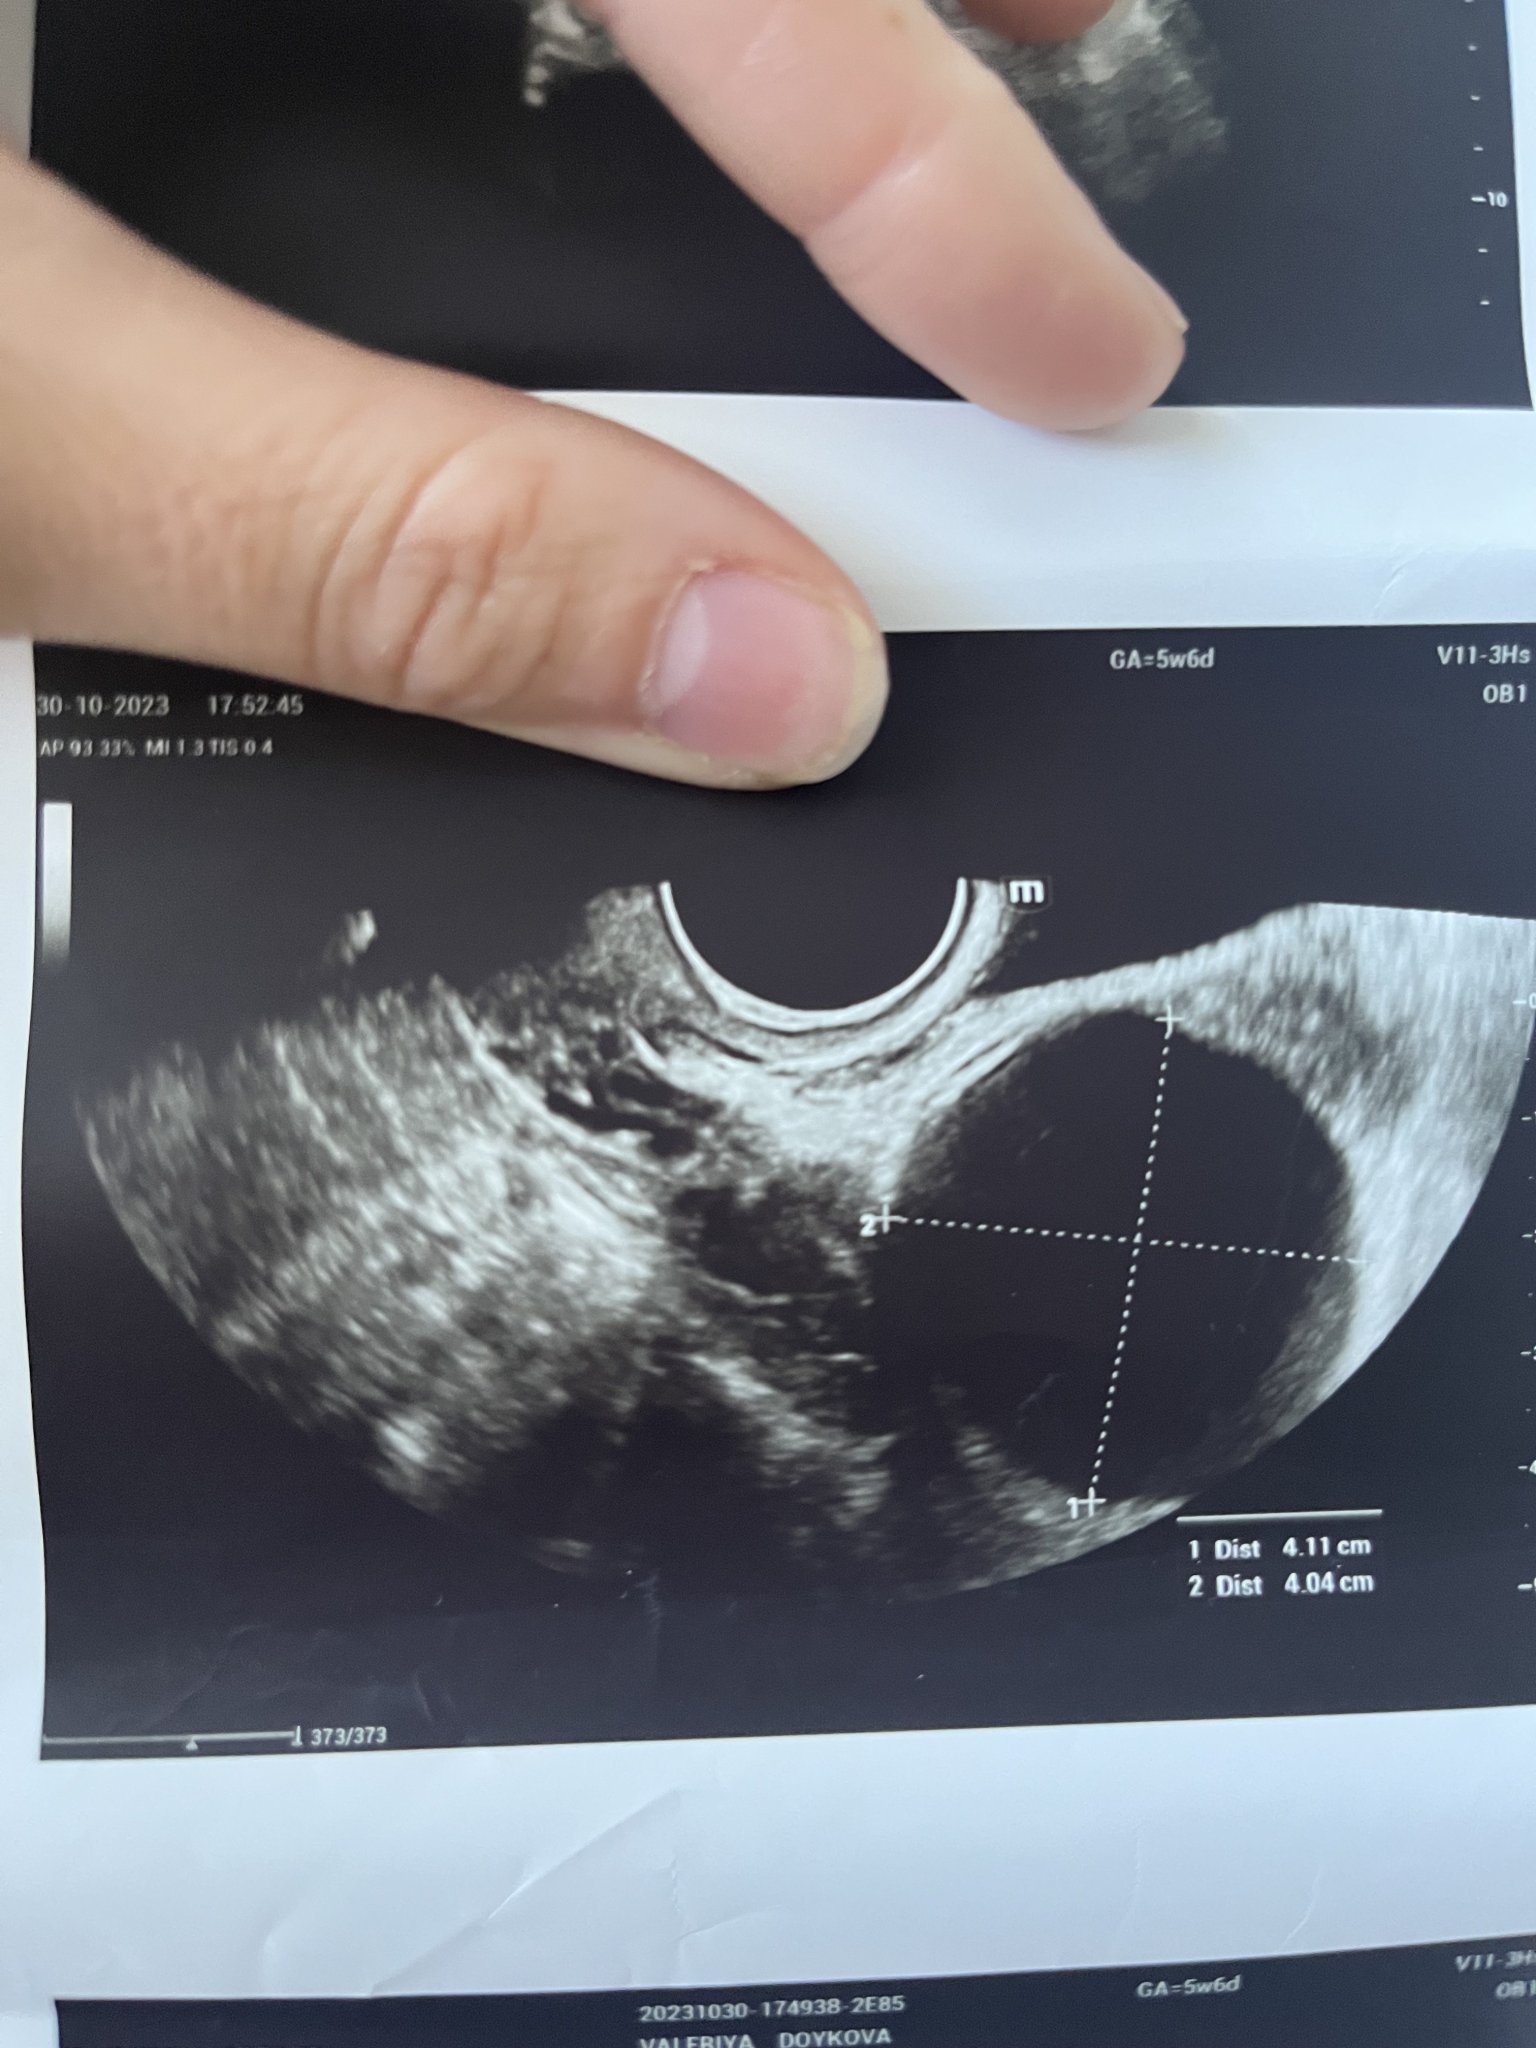

Първия ден на последната ми менструвация беше на 19.09.2023г. 4 положителни теста за бременност. Вччера беше първият ми преглед. Прикачам снимките от него. Видя се плоден сак с размер 18мм, ембрион не. Аз съм с две матки и плодния сак е в лявата матка. В левия яйчник имам и 40мм киста Sad . Притеснено ми е защо при тази големина на плодния сак не се видя ембрион. Преди 8 месеца претърпях куха беменност и се притеснявам изключително много да не се повтори. Чак след месец ще ми бъде следващия преглед, а до тогава ще се побъркам. Моля, ако някой може да помогне със съвет или е бил в подобна ситуация, да пише. Благодаря! Simple Smile

Може да се дължи на късна овулация. Но по принцип след 6г.с. може да се визуализира нещо (зависи и от техниката), Вие сте в 5+6 г.с. според снимката. Ако имате възможност отидете точно след седмица на преглед. Би трябвало всичко да е наред, стискам палци!